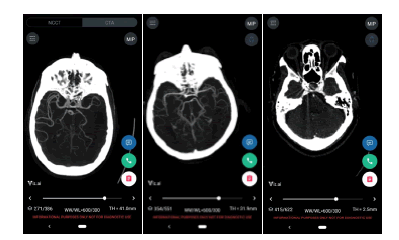

In a new ruling in February of 2018 [5], the United States Food and Drug Administration (FDA) approved Viz LVO and thus created a new category of medical devices: computer assisted triage (CADt). Viz LVO is an artificial-intelligence powered software application which automatically analyzes computed tomography angiography (CTA) of the brain of patients suspected of stroke, identifying large vessel occlusions (LVO) and flagging them directly to a specialist, who can make a treatment decision or guide the team to further investigate the differential diagnosis. Screenshots of the device are provided in [Figure 1]. This device creates a parallel workflow that has the potential to significantly accelerate diagnosis and treatment, as outlined in [Figure 2]. The supporting evidence for the FDA submission included real-world data demonstrating a significant time savings, alerting the specialist on average 52 minutes faster than the standard of care.

Figure 1: The Viz LVO device offers automatic stroke detection and notification (left), coupled with a mobile DICOM viewer (right).

A total of 163 ground-truth LVOs were identified. The overall sensitivity and specificity were 96.32% [0.9268, 0.9884] and 93.83% [0.9283, 0.9475], respectively. The median time to notification of the software was 5 minutes and 45 seconds, discounting 7 historical cases which were sent to the device manually for testing. 4.14% of scans were rejected by the device due technical reasons such as metal artifacts in close proximity to the Circle of Willis, and were therefore excluded from the analysis. Summary of performance statistics is provided in [Table 2]. Examples of device outputs are provided in [Figure 3].